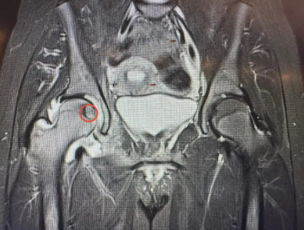

تدخل علاجي نوعي في مستشفى الجامعة لعلاج ورم في رأس عظم الفخذ